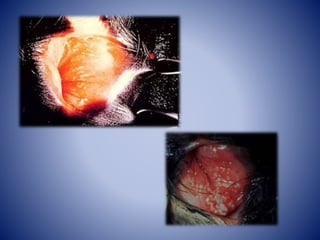

• Vulvovaginitis pustular infecciosa (IPV) es una

inflamación pustular causando enrojecimiento y

edema de la mucosa genital con vesículas y

pústulas evolucionando a úlceras.

La lesión primaria consiste en una necrosis focal de

las membranas mucosas genitales. Esta lesión es,

probablemente, la secuela directa de la replicación

del virus.